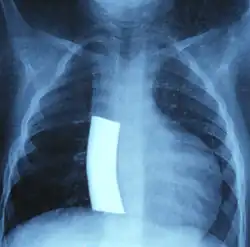

Obecnie operacja Fontana jest najczęściej dwuetapową operacją, stosowaną jako drugi i trzeci etap procedury Norwooda. Zabieg polega w pierwszym etapie na wykonaniu dwukierunkowego zespolenia Glenna, lub tzw. operacji hemi-Fontana. Krew z żyły głównej górnej (VCS) spływa bezpośrednio do tętnic płucnych, a z żyły głównej dolnej (VCI) miesza się nadal z krwią tętniczą na poziomie serca. W drugim etapie operacji Fontana wykonuje się najczęściej zewnątrzsercowe połączenie VCI z tętnicą płucną lub połączenie wewnątrzsercowe (tzw. operacja de Levala – Total Intracardiac Cavo−Pulmonary Connection). Od tego momentu krążenie duże (systemowe) i małe (płucne) są oddzielone, gdzie krew żylna przepływa przez płuca pod wpływem ciśnienia żylnego, a krew tętnicza pompowana jest do aorty przez pojedynczą komorę serca[2]. Najczęściej stosuje się dwie modyfikacje operacji Fontana:

- zewnątrzsercową (obecnie preferowaną), gdzie żyłę dolną główną łączy się z prawą gałęzią płucną przy użyciu protezy wykonanej z Gore-Texu[2][12][13]. Po wprowadzeniu przez Marcellettiego w 1990 zewnątrzsercowego zespolenia VCI z tętnicą płucną metoda ta jest aktualnie metodą z wyboru (polecana jako najlepsza) i jest przeprowadzana najczęściej w krążeniu pozaustrojowym na bijącym sercu, ale może być też wykonana przy przeciwwskazaniach, bez użycia krążenia pozaustrojowego stosując na czas zespolenia omijające połączenie między VCI i prawym przedsionkiem serca[2][14].